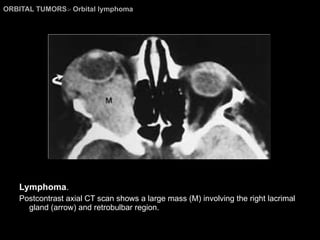

Orbital Lymphoma The CT and MR imaging findings; Usually nonspecific:  impossible to differentiate from  orbital pseudotumors, lacrimal gland tumors, optic nerve tumors, Graves’ orbitopathy, primary orbital tumors, or orbital cellulitis. Homogeneous masses of relatively high density and sharp margins. More often seen in the anterior portion, the retrobulbar area, or in the superior orbital compartment.  Mild to moderate enhancement.

Orbital Lymphoma The CT and MR imaging findings; Mold themselves around the orbital structures without producing bony erosion.  However, the aggressive malignant lymphomas can produce frank destruction of bone. Both pseudotumors and lymphoma may have intermediate or low signal intensity on T1WI and appear isointense to fat on T2WI.

ORBITAL TUMORS >  Orbital lymphoma Lymphoma . Postcontrast axial CT scan shows a large mass (M) involving the right lacrimal gland (arrow) and retrobulbar region.